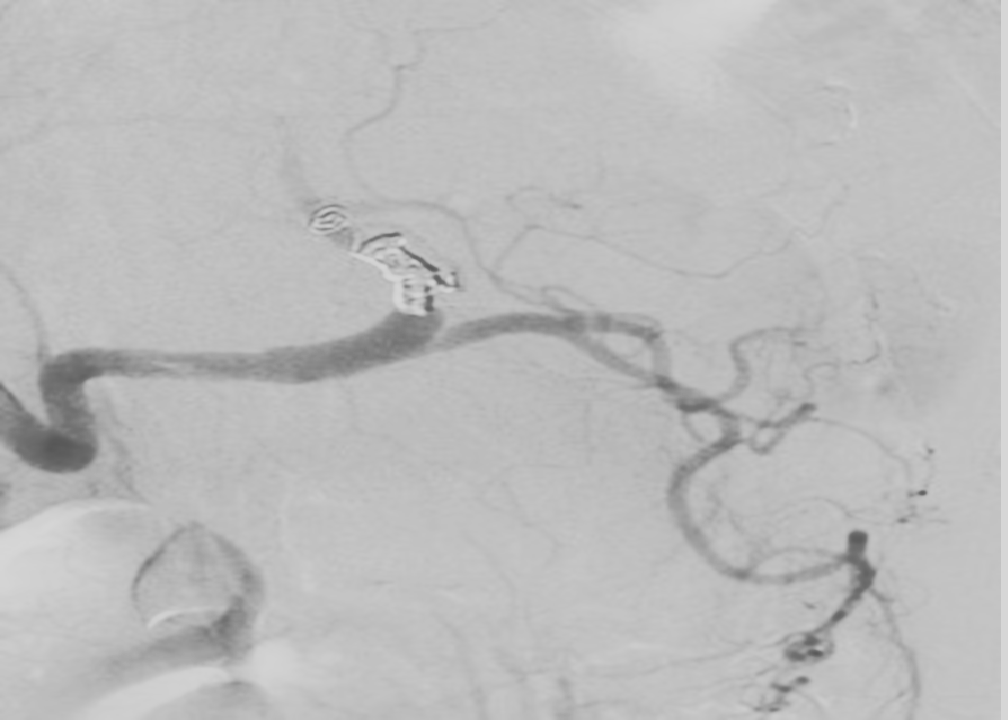

Partial Splenic artery embolization in hypersplenism patient achieve infarction in 60–70 % of the splenic mass

A lesser extent of infarction allows reduced sequestration and destruction of the blood elements, maintenance of the spleen’s immunologic function (it’s the site where antibodies , monocytes and activated lymphocytes are produced ), and preservation of antegrade flow in the splenic vein.